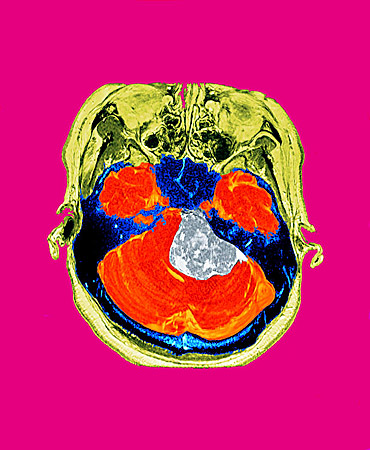

2021年、脳腫瘍の手術の際、記念に貰った脳のMRI画像で作成した作品を出展したのを機に、思いつくまま気の向くまま、色んなギャラリーさんに展示して頂いた写真が結構たまってきました。